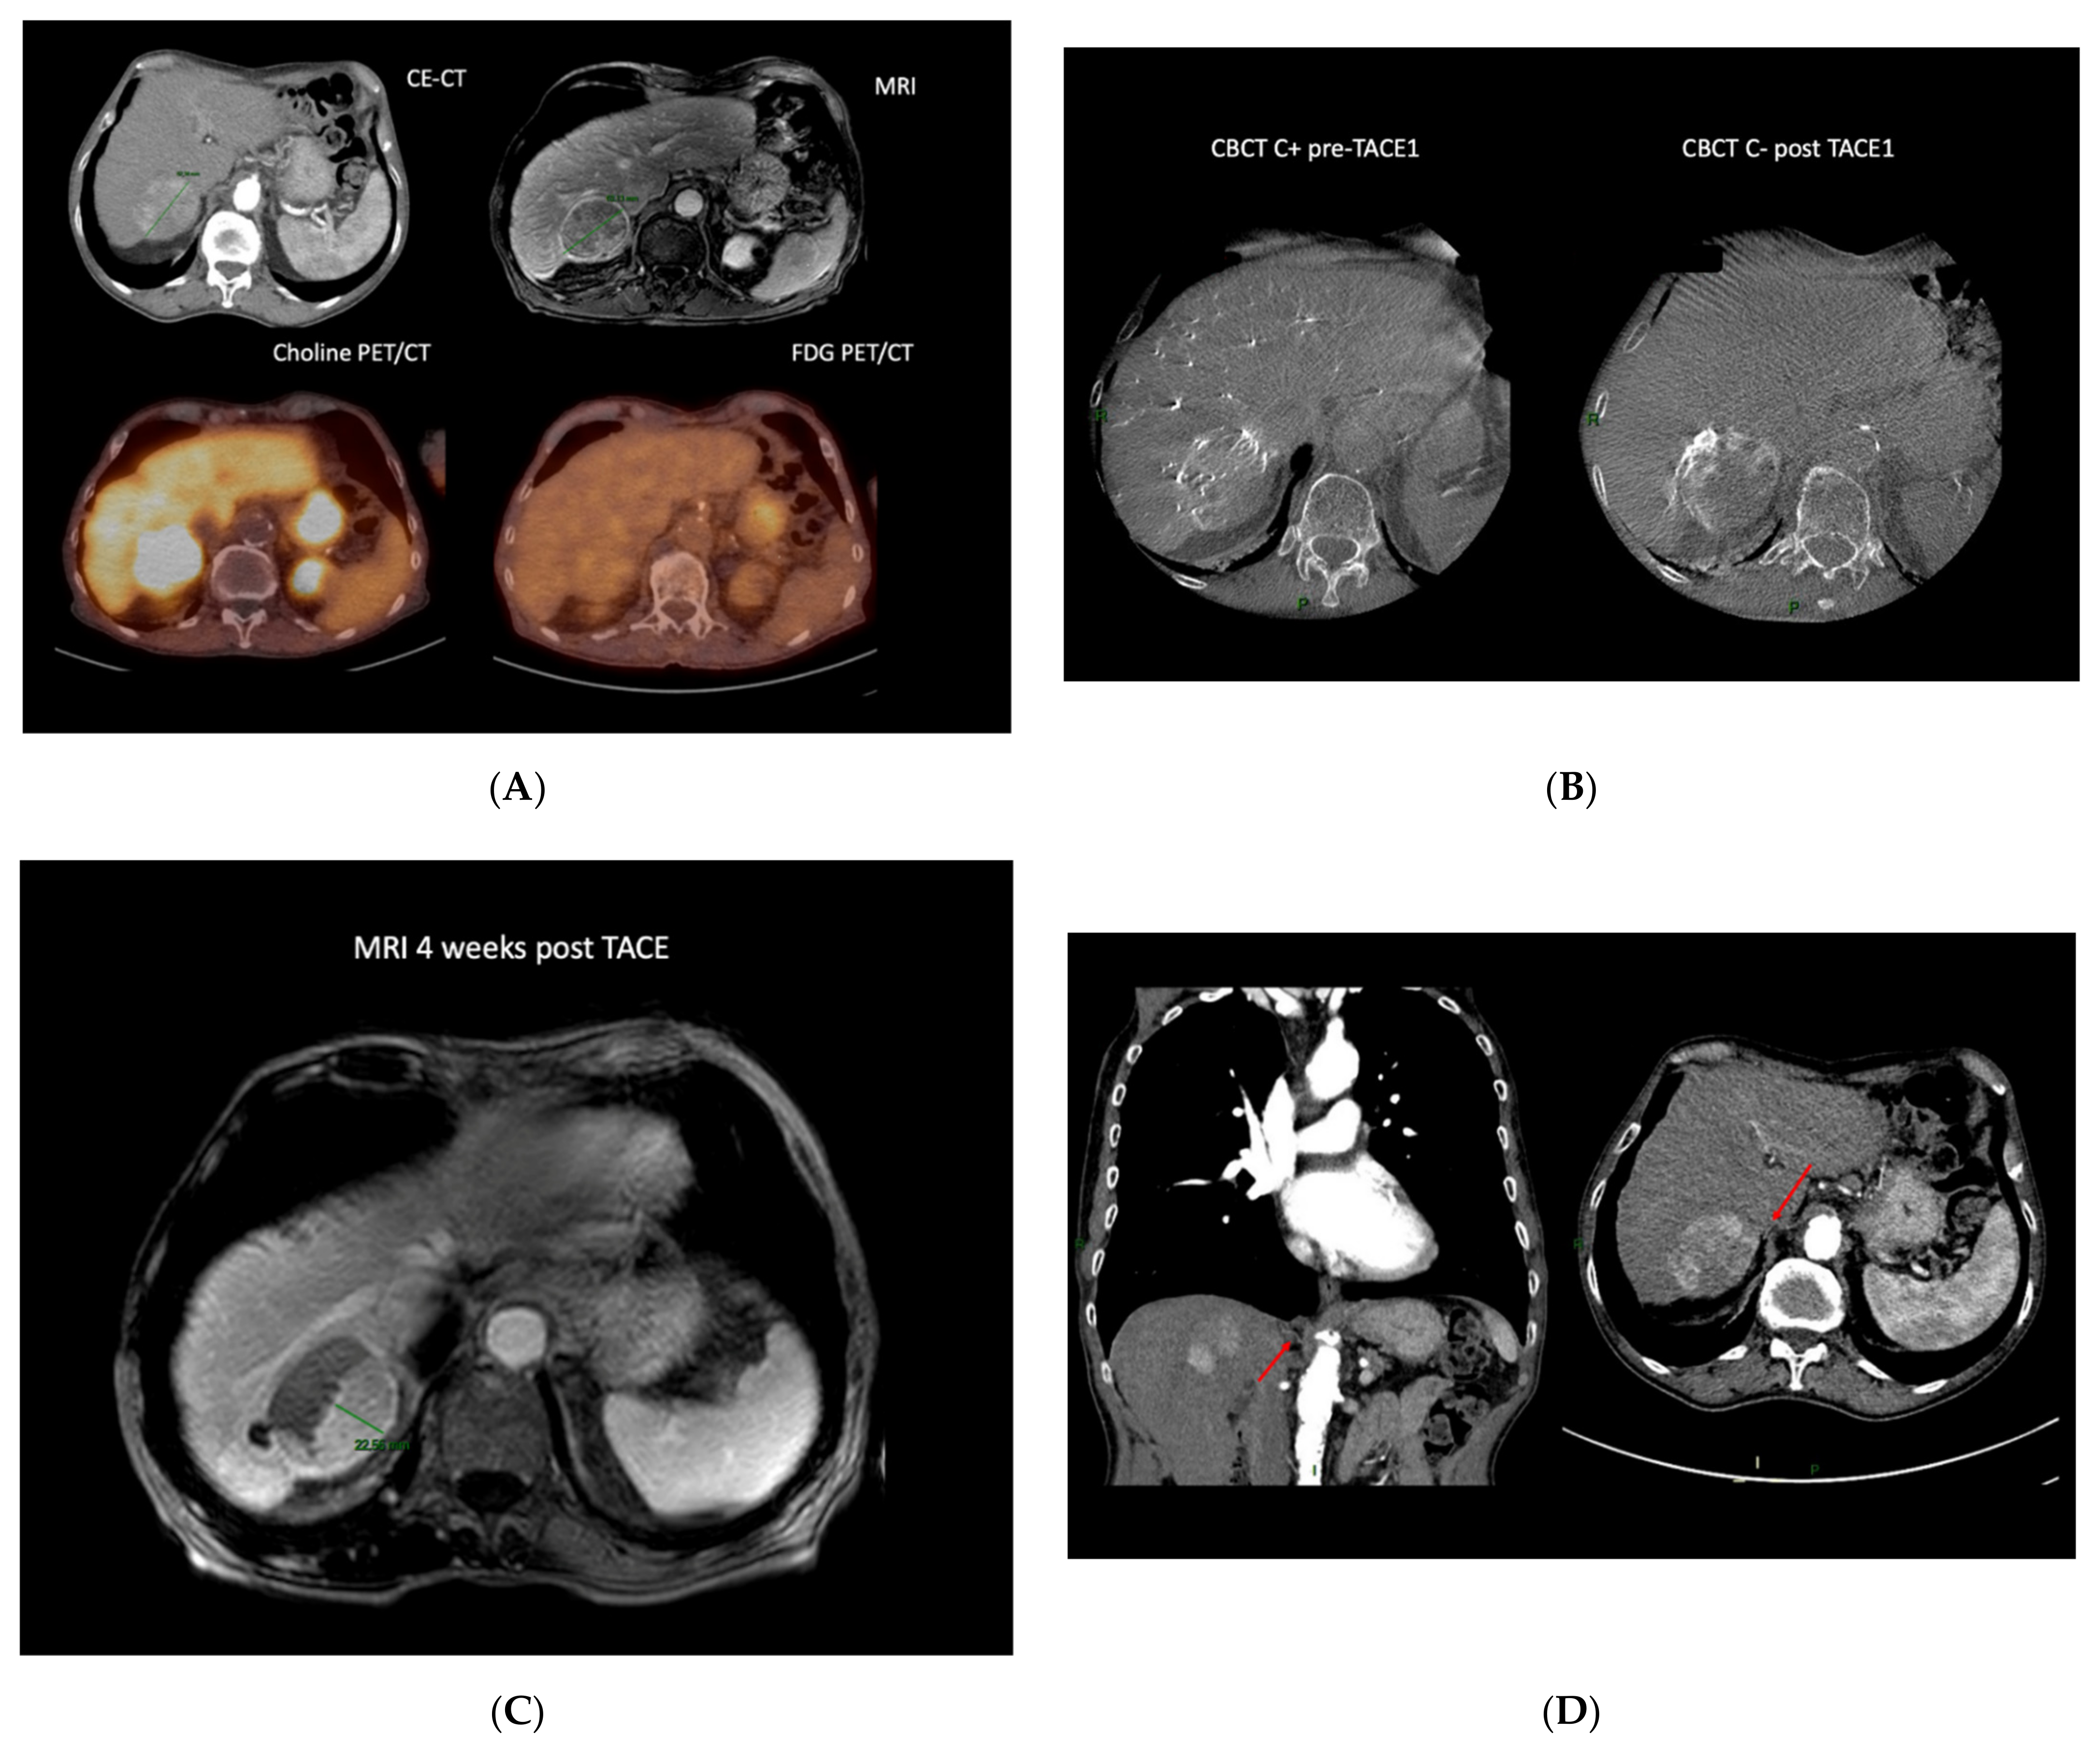

Moreover, it can be used for the detection of remnant viable tumor after TACE (Figure 1).

Case example of an 80-year-old patient diagnosed with a 62 mm HCC developed on cirrhosis (chronic hepatitis C). The work-up disclosed no distant metastasis. He underwent a double PET CT (FDG and choline) that showed a choline positive intake, suggesting a well-differentiated tumor (A). Due to multiple comorbidities, he could not undergo surgery; therefore, after a multidisciplinary discussion with the hepatic board, TACE was recommended. The enhanced CBCT performed before TACE showed sub-optimal treatment, with 30% of the lesion not being treated, which was confirmed on non-enhanced CBCT post DEM administration (B). The control MRI at 1 month showed a partial response with a 22.5 mm residual tumor (C). The patient had a CE-CT that showed a particular anatomy, with the non-responding side of the tumor being vascularized by a right phrenic artery (D). The patient underwent a second TACE, but unfortunately, the small artery could not be catheterized. Due to his general status, the patient benefited from BSC. (CE-CT: computed tomography; MRI: magnetic resonance imaging; Choline PET/CT: Choline positron emission tomography; FDG PET/CT: 18F-fluorodeoxyglucose positron emission tomography; CBCT C+: contrast enhanced cone-beam computed tomography; CBCT C-: non-enhanced cone-beam computed tomography; TACE: trans-arterial chemoembolization.)

In a retrospective evaluation in 2011, Iwazawa et al. depicted that C-arm CT is nearly equivalent to biphasic multidetector computed tomography (MDCT) for detecting incomplete iodized oil accumulation after cTACE; more precisely, they determined that it helps to recognize a suboptimal treatment immediately post TACE [99]. Several studies followed, supporting these findings [100,101], among which was a recent retrospective analysis by Orlacchio et al. that assessed the ability of CBCT to predict short-term response at the 30-day follow-up CT after TACE [102]. Evaluation of the area under the ROC curve showed that the diameter, volume, and density of the lesion measured with CBTC had an accuracy of 94%, 96%, and 98%, respectively, in discriminating a complete response from a not complete response. As mentioned earlier, tumor response is the most important predictive factor of survival; this early assessment of treatment is key to future patient management. Choi et al. also found an advantage of using CBCT immediately after TACE for assessing response and for predicting the response outcome [103].